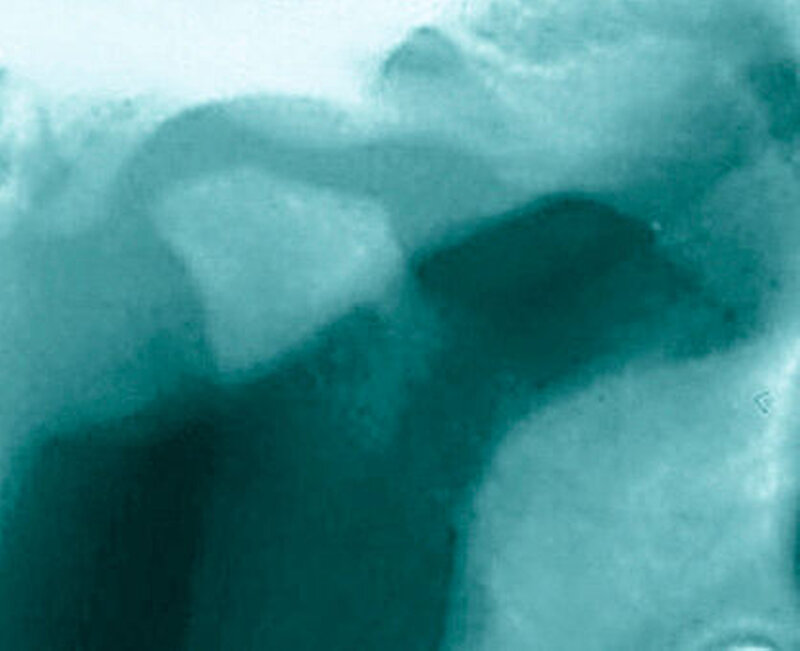

Bereits 2004 wies Carla Evans [Evans, 2005] auf das Risikomanagement bei Allgemeinerkrankungen hin und stellte am Beispiel der JIA dar, dass Unterkieferrücklagen und frontal offene Bisse aus der Kiefergelenkzerstörung entstehen können. Die Röntgenaufnahmen einer JIA-Patientin mit oligoartikulärer Form und Beteiligung des rechten Kiefergelenkes zeigen den typischen Verlauf sehr gut. Bei ursprünglich sehr dezenten Befunden, wie einer s-förmigen Mundöffnung von 44 mm, einer geringen Mittenabweichung um 2 mm nach rechts und einem frontal offenem Biss klagte sie über Schmerzen beim Essen, was den Anlass zur weiteren Diagnostik bot. Die erste Panoramaröntgenschichtaufnahme (Abbildung 1a-c) zeigt auf der rechten Seite einen abgeflachten Kondylus und eine bereits verstrichene Fossa condylaris. Ein Jahr später vermittelt das Fernröntgenseitenbild (Abbildung 1d) trotz fortschreitender kondylärer Resorption ein harmonisches Bild, während nach drei Jahren bei voranschreitendem Abbau des rechten Kondylus (Abbildung 1e) eine Rücklage der Mandibula und eine Bissöffnung manifest sind (Abbildung 1f).

Bei 152 durchschnittlich 12-jährigen Rheumapatienten wurden die kondyläre Morphologie und Symmetrie beziehungsweise Asymmetrie im Vergleich zu einer Kontrollgruppe anhand der OPG analysiert. Zur Analyse erfolgte die Zuordnung zu vier morphologischen Graden je Kondylus (Abbildung 3a-d). Bei 45 Prozent der Rheumapatienten waren morphologische Veränderungen im Rahmen kondylärer Resorption unterschiedlicher Ausprägung zu finden. Die „Kontrollpatienten“ ohne JIA zeigten nur zu 14 Prozent formatypische Kondylen. Der Unterschied zwischen den beiden Gruppen war signifikant. Daher sollte bei der Routineauswertung von Panoramaröntgenschichtaufnahmen auf diese Anzeichen geachtet werden, insbesondere auch unter dem Aspekt, dass laut Assaf [2011] durchschnittlich 4,3 Jahre zwischen Erstmanifestation der JIA und Erstvorstellung in der Rheumasprechstunde des UKE liegen.